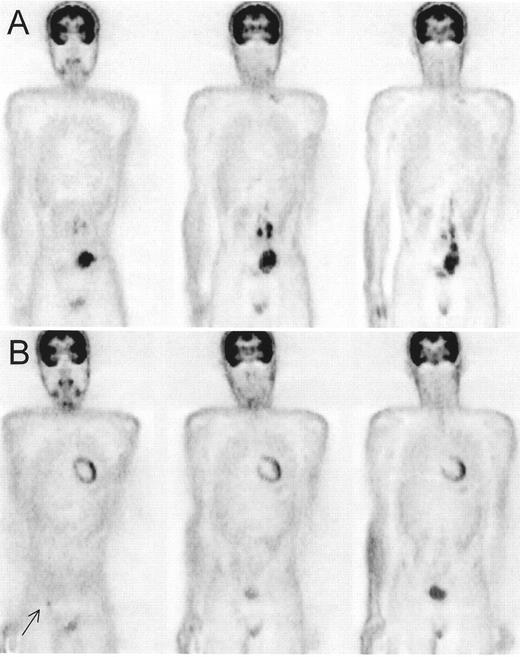

Positron emission tomography (PET) scan of a patient with Hodgkin’s lymphoma, nodular sclerosis, stage IIIB, prior to the start of chemotherapy (A).

PET after therapy (B) showed a complete normalization of the initially involved sites, but a new hot spot developed in the right groin (→). Correlation with clinical history revealed erysipelas of the right leg with probably inflammatory nodes in the groin. Repeat PET scan after antibiotics was completely normal. The patient remains in complete remission after a follow-up of 4 years.